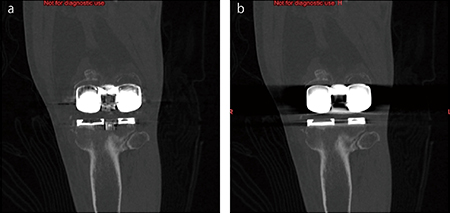

■症例1 人工関節置換術後(左膝関節)

a:SEMARあり、b:SEMARなし

SEMARの画像再構成を行うことで、軟部組織や関節腔の描出能も大幅に改善されている。